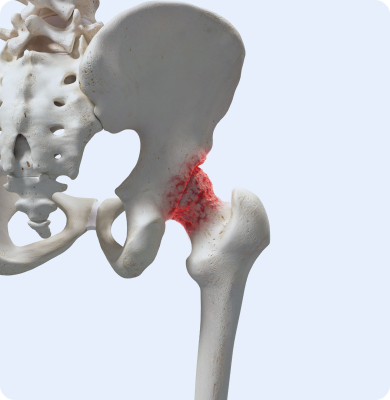

고관절 부위의 대퇴골과 골반 뼈가 파손되는 질환

주로 낙상 사고, 교통사고 등 외상에 의해 발생하며 골다공증으로 인한 뼈의 약화가 주요 원인입니다.